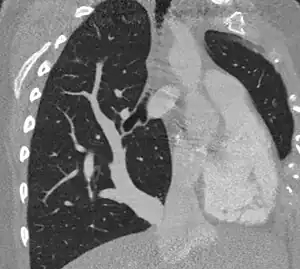

Scimitar syndrome chest CT | |

Scimitar syndrome, or congenital pulmonary venolobar syndrome, is a rare congenital heart defect characterized by anomalous venous return from the right lung (to the systemic venous drainage, rather than directly to the left atrium).[1] This anomalous pulmonary venous return can be either partial (PAPVR) or total (TAPVR). The syndrome associated with PAPVR is more commonly known as Scimitar syndrome after the curvilinear pattern created on a chest radiograph by the pulmonary veins that drain to the inferior vena cava.[2] This radiographic density often has the shape of a scimitar, a type of curved sword.[2] The syndrome was first described by Catherine Neill in 1960.[3]

The anomalous venous return forms a curved shadow on chest x-ray such that it resembles a scimitar. This is called the Scimitar Sign. Associated abnormalities include right lung hypoplasia with associated dextroposition of the heart, pulmonary artery hypoplasia and pulmonary sequestration. Incidence is around 1 per 100,000 births.[4]

The diagnosis is made by transthoracic or transesophageal echocardiography and selective pulmonary angiography.[6] More recently by CT angiography or MR Angiography.